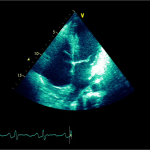

Ecocardiografia transtoracică

- Formaţiune hiperecogenă cu suprafaţa neregulată, care tapetează peretele liber al VD, grosime de 12 mm

- Dispusă de sub planul valvei tricuspide până in apropierea conului de ejecţie al valvei pulmonare

- SIV aplatizat

Ecografia transesofagiană:

Confirmă datele de la ecografia transtoracică